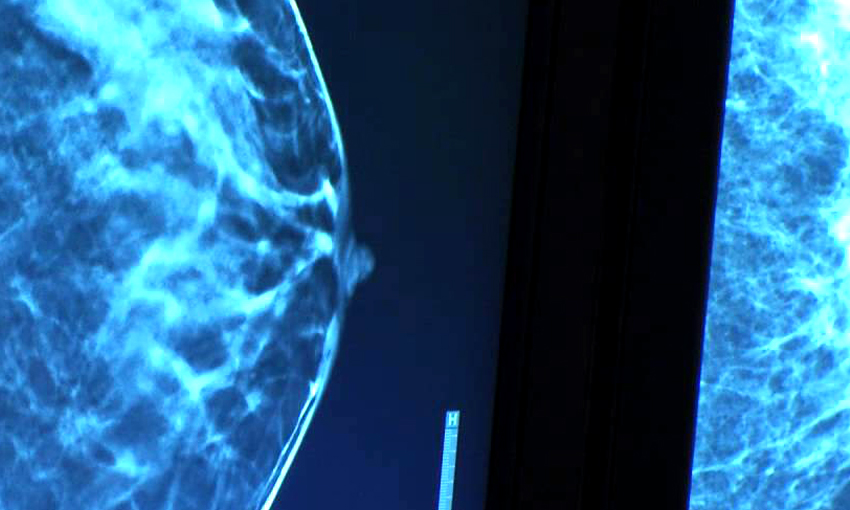

O melhor método de imagem para fazer o diagnóstico precoce é a mamografia. Inúmeros estudos já demonstraram que realizar mamografia anual reduz em pelo menos 30% a mortalidade pelo câncer de mama. Por isso, este é o exame mais indicado e fundamental para o rastreamento do câncer de mama (exame de rotina).

A mamografia evoluiu ao longo dos anos, passando da mamografia de alta resolução para a mamografia digital e recentemente para a mamografia digital com tomossíntese. A tomossíntese não é um novo exame, mas uma ferramenta disponível nos mamógrafos mais novos e modernos, onde se consegue gerar um tipo de imagem 3D, melhorando a detecção do câncer. Desta maneira, deve-se considerar incluir a mamografia com tomossíntese no rastreamento sempre que possível, ou disponível.

A ultrassonografia pode ser usada de maneira complementar (e não substitutiva) à mamografia, principalmente quando a mama for densa, ou seja, quando a composição da mama apresentar mais glândula que gordura.

- o melhor método de imagem ainda é a mamografia digital e deve-se considerar incluir a tomossíntese (uma ferramenta dos melhores aparelhos de mamografia) no rastreamento sempre que possível, ou disponível;

- o rastreamento complementar com ultrassonografia deve ser incluído sempre que a mama da mulher for densa;

A densidade maior ou menor da mama ganha importância na análise da mamografia. Nesse momento, o médico radiologista precisa determinar o quão densa é a mama e para isso a classifica segundo 4 categorias que variam de mamas extremamente densas a mamas extremamente adiposas. Quanto mais densa é a mama, mais branca ela aparece na mamografia. Sabendo-se que lesões mamárias (incluindo o câncer) também são brancas na mamografia, conseguimos entender que quanto mais densa a mama, mais difícil é a leitura desse exame pelo médico e, portanto, mais fácil é uma lesão ou outra passar desapercebida.

Esse fato, em conjunto com os dados da literatura de que a alta densidade mamária pode aumentar o risco de câncer de mama em torno de 1,2 a 2 x (comparado com a média), tornam a mulher com mamas densas foco de especial atenção dos médicos. Nesse grupo de mulheres, é fundamental uma análise minuciosa e muitas vezes a complementação da mamografia com a tomossíntese (mamografia 3D), ultrassonografia ou, em casos específicos, a ressonância magnética.

Tomossíntese (ou mamografia 3D) é uma nova tecnologia de imagem digital da mama, com baixa dose de radiação. O exame é realizado no mesmo aparelho de mamografia digital e o tempo de duração é praticamente o mesmo. A mama é comprimida como na mamografia convencional, em posição mediolateral oblíqua. Em seguida, é feita uma varredura de toda a mama (o tubo de RX movimenta-se em ângulo pré-determinado, como um arco), gerando várias imagens que serão imediatamente transmitidas ao computador para reconstrução. O médico radiologista poderá avaliar todas as imagens geradas na estação de trabalho.

Estudos têm mostrado que a tomossíntese reduz significantemente a superposição dos tecidos da mama, sobretudo em mamas mais densas, melhorando a identificação de lesões e permitindo diferenciar lesões verdadeiras daquelas que seriam geradas por esta superposição dos tecidos normais. Com isso, há uma menor reconvocação das pacientes para estudo complementar e uma redução expressiva do número de resultados falso-positivos e biópsias desnecessárias. Outra grande vantagem da tomossíntese é a maior sensibilidade em detectar microcalcificações e tumores invasivos em estágio inicial.

Publicações recentes mostram que a tomossíntese, associada à mamografia digital nos exames de rastreamento, resulta em uma taxa de detecção do câncer mais elevada, além do diagnóstico de maior número de tumores invasivos, quando comparada ao uso da mamografia convencional.